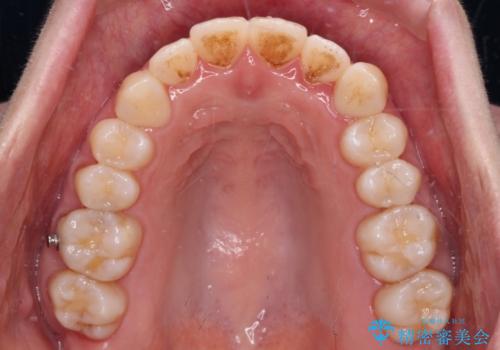

- 受け口傾向でクロスバイトの前歯を治したいとのことで来院された患者様です。

下顎骨が若干左側に変位していたため、右側にアンカースクリューを使用し、積極的に移動させながらインビザラインにて矯正治療を行うこととしました。

インビザラインによる矯正治療は、受け口傾向の治療に非常に適した方法であり、事前にシミュレーションに沿って治療を進めることできます。

今回の治療では骨格的な偏位があったためアンカースクリューを使用し、より確率の高い治療を行うことができました。